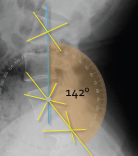

Q what is the name of this measurement? and what is the average + range?

A: Lumbosacral lordosis angle

assesses the angle between the lumbar and sacral spine. The average is 146°, with a range of 124-162°.